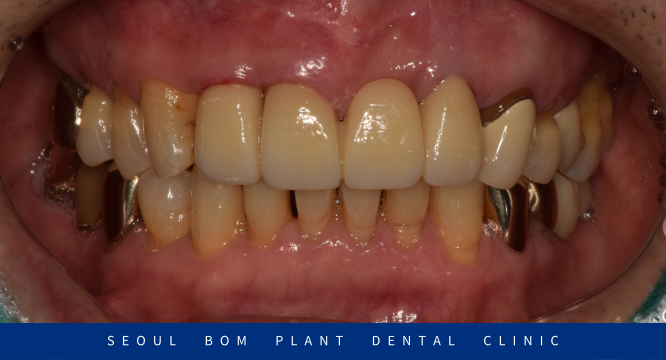

앞니 보철물 수복이 마무리된 구강 내 사진인데요.

환자분께서는 색상, 모양 모두 마음에 드신다며

바로 붙여달라고 하셨지만

자연광이나 밝고 어두운 곳에서의 색상도 확인해 보는 것이 좋다고 판단되어

임시로 접착하여 일생 생활에서 사용해 보시면서

거슬리거나 불편한 부분이 없는지 체크해 본 다음에

완전히 붙여드리기로 하였습니다.

며칠 사용해 보시더니 불편한 거 없으셨고

치료 전보다 훨씬 더 심미적으로 변해서

오히려 마음에 든다며 말씀해 주셔서

보철물을 완전히 붙여드리면서 치료를 마무리해 드렸습니다.